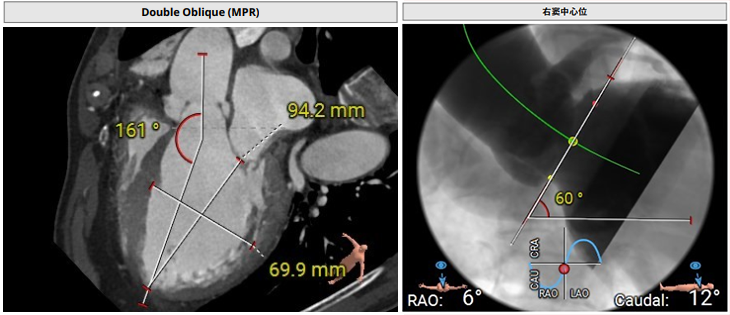

术前影像评估提示,患者主动脉瓣为三叶瓣结构,瓣叶基本等大,左右瓣稍有粘连,瓣叶中度增厚,游离缘轻微钙化。主动脉瓣环直径31.0mm,左心室流出道直径36.4mm,STJ直径33.8mm,升主动脉直径38.8mm,左冠脉开口高度偏低(9.1 mm),左冠瓣瓣叶长约19.4mm,存在术中冠脉阻塞潜在风险,右冠脉开口高度充足,瓣叶长约18.0mm,左室与主动脉夹角161°,心脏角度60°。

CTA评估(上下滑动查看更多照片)

瓣膜选型:JS/TAVI-31瓣膜